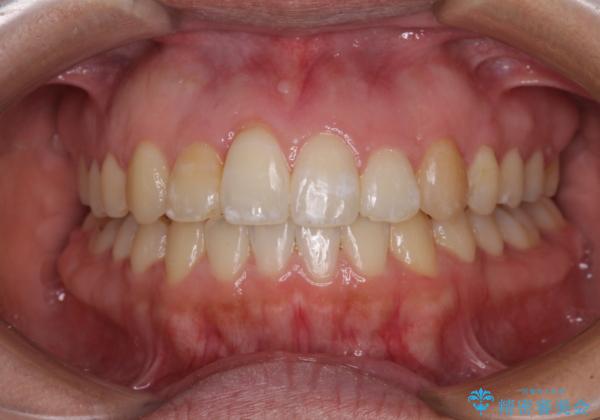

- 上下のデコボコを改善したいとのことで来院された患者様です。

近々妊娠する予定であり、極力短期間で治療したいとのことで、ワイヤー装置による非抜歯矯正治療を行うこととしました。

治療開始後すぐに妊娠され、つわりと闘いながらの矯正治療となりました。

上下顎でゴムかけを行ったのですが、早く終わらすためにしっかりと装着していただき、無事出産前に装置を外すことができました。